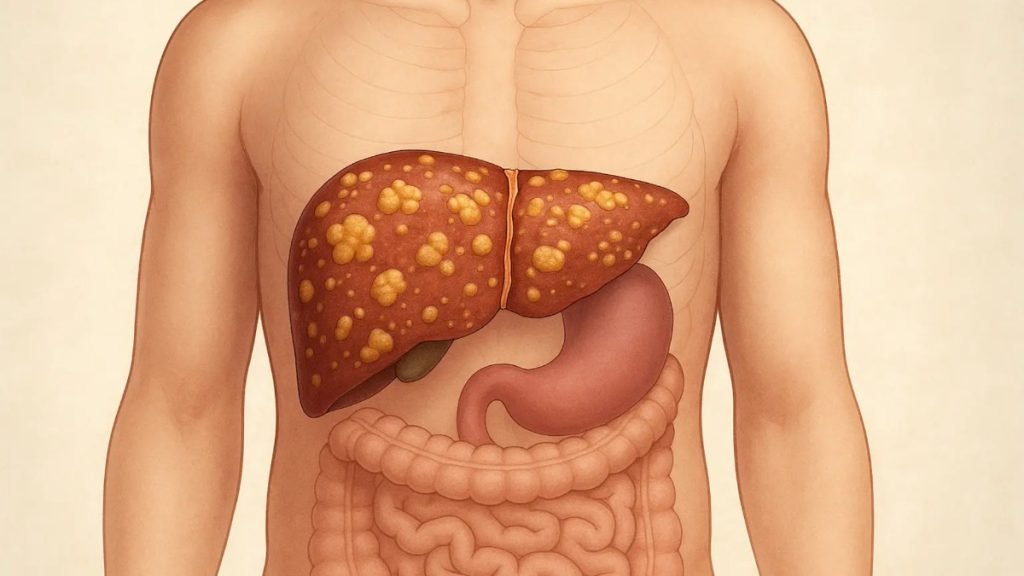

- 🧬 लिवर में सूजन (Inflammation)

फैटी लिवर बढ़ने पर लिवर में सूजन आ जाती है, जिसे NASH (Non-Alcoholic Steatohepatitis) कहा जाता है।

- ⚠️ लिवर सिरोसिस का खतरा

अगर लंबे समय तक इलाज न किया जाए, तो फैटी लिवर लिवर सिरोसिस जैसी गंभीर बीमारी में बदल सकता है, जिसमें लिवर स्थायी रूप से खराब हो जाता है।